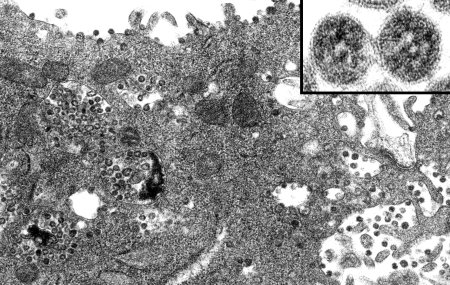

Рисунок представляет собой электронный микрофотоснимок клетки печени животного. Это изображение может быть использовано для заполнения таблицы или анализа структуры и состояния клетки печени. Визуальные данные, полученные с помощью электронной микроскопии, позволяют увидеть мельчайшие детали клеточных компонентов и органелл. Результаты такого анализа могут быть полезными для изучения болезней печени или проведения научных исследований в области биологии и медицины.